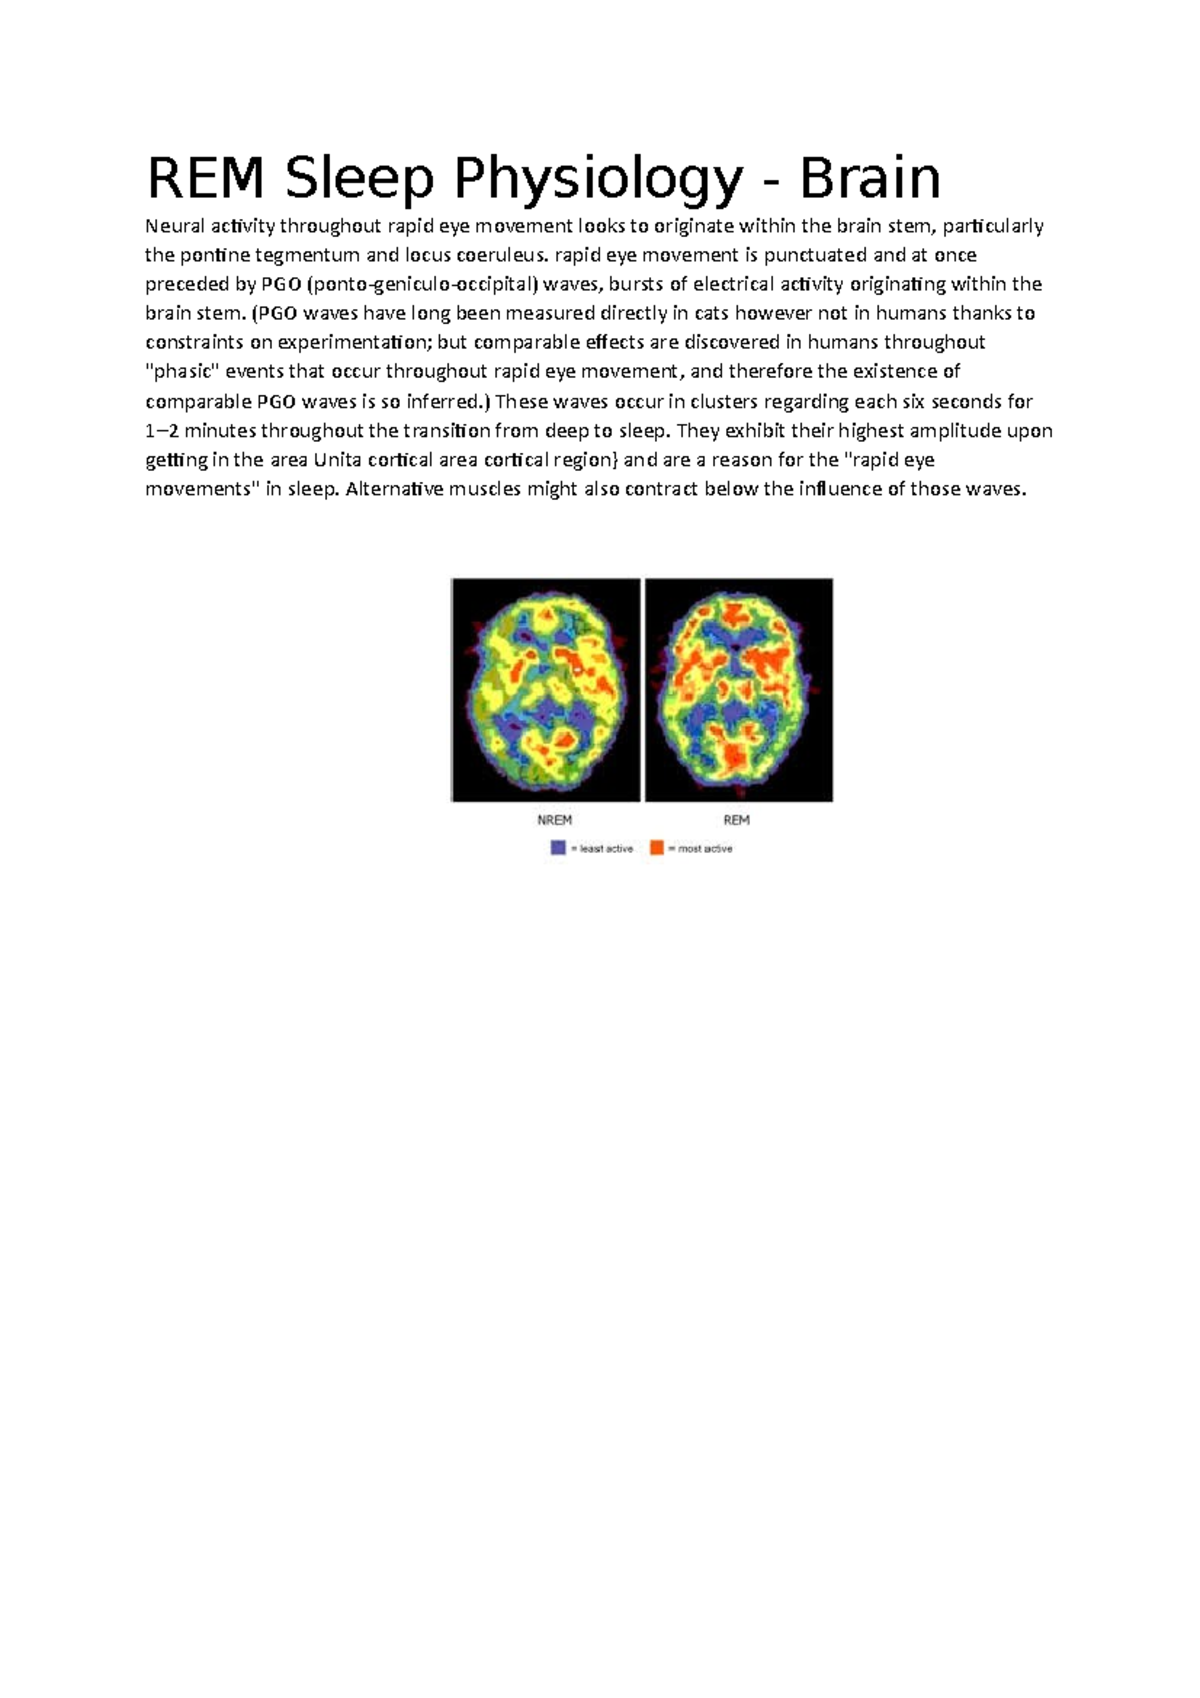

(a) Functional neuroanatomy of REM sleep. Brain regions more activated Rem Sleep Physiology The human body cycles through 2 phases of sleep, (1) rapid eye movement (rem) and (2) nonrapid eye movement (nrem) sleep,. The human body cycles through 2 phases of sleep, (1) rapid eye movement (rem) and (2) nonrapid eye. Most adults need about two. Each phase and stage represents the relative. Nrem sleep is subdivided into several stages numbered 1. Rem Sleep Physiology.